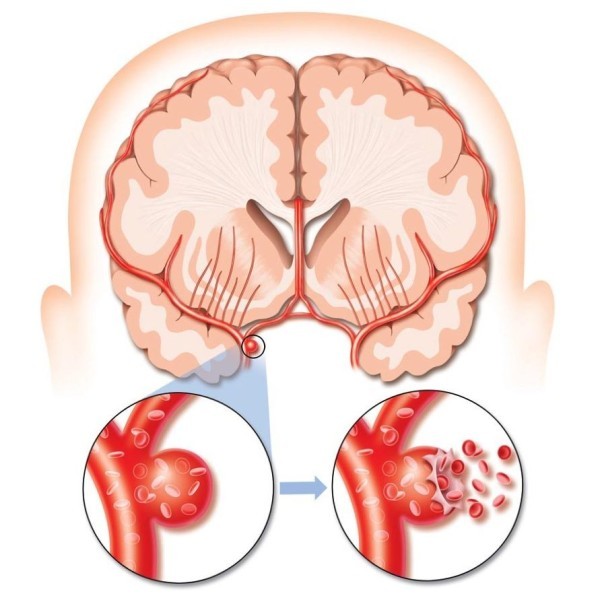

Артериальные аневризмы головного мозга – мешковидное (иногда сферообразное) выпячивание стенки кровеносного сосуда. Исходя из анатомических особенностей строения артериальной стенки, можно сказать, что процесс ее образования затрагивает все три слоя сосуда: внутреннюю – интиму, мышечную прослойку и наружную – адвентицию.

Развитие дегенеративных процессов, нарушение развития того или иного слоя может привести к потере эластичности его определенного участка. Основным последствием таких нарушений является выпячивание части сосуда из-за давления, которое оказывает на него ток крови.

Как правило, аневризмы располагаются в месте бифуркации (раздвоения основного ствола) артериальных сосудов, так как в этом участке давление достигает своего максимума.

Основными компонентами самого выпячивания являются шейка, тело и купол. Первая часть аневризм сосудов головного мозга, как и сама артерия, имеет три слоя.

Купол – самое слабое место, которое состоит только из интимы, как правило, разрыв происходит именно на этом участке. Зачастую нарушение целостности мешка наблюдается у больных в возрасте 50+.

На фоне развития атеросклероза и постоянного повышения артериального давления выпячивание не выдерживает такую нагрузку, и его стенка прорывается в полость черепной коробки.